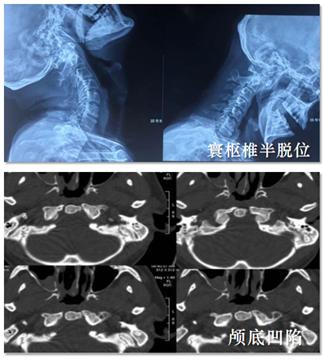

颈椎受累主要有以下三种表现:寰枢椎半脱位(65%)、颅底凹陷症(20%)、下颈椎半脱位(15%)。

寰枢椎半脱位也称为C1-C2不稳定性。半脱位可以发生在多个平面上,因此前、后、侧和旋转性半脱位都有可能,但大多数半脱位发生在前方。

颅底凹陷是由于枕骨C1和C1-C2的侵蚀导致齿状突和脑干之间的垂直距离减小。这可能导致严重的神经损伤。

图5 颈椎受累▌ 足关节受累